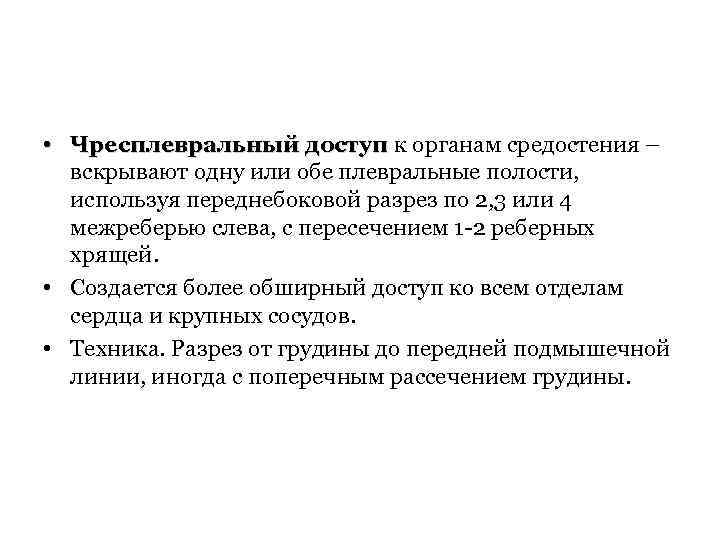

• Чресплевральный доступ к органам средостения – вскрывают одну или обе плевральные полости, используя переднебоковой разрез по 2, 3 или 4 межреберью слева, с пересечением 1 -2 реберных хрящей. • Создается более обширный доступ ко всем отделам сердца и крупных сосудов. • Техника. Разрез от грудины до передней подмышечной линии, иногда с поперечным рассечением грудины.

• Чресплевральный доступ к органам средостения – вскрывают одну или обе плевральные полости, используя переднебоковой разрез по 2, 3 или 4 межреберью слева, с пересечением 1 -2 реберных хрящей. • Создается более обширный доступ ко всем отделам сердца и крупных сосудов. • Техника. Разрез от грудины до передней подмышечной линии, иногда с поперечным рассечением грудины.